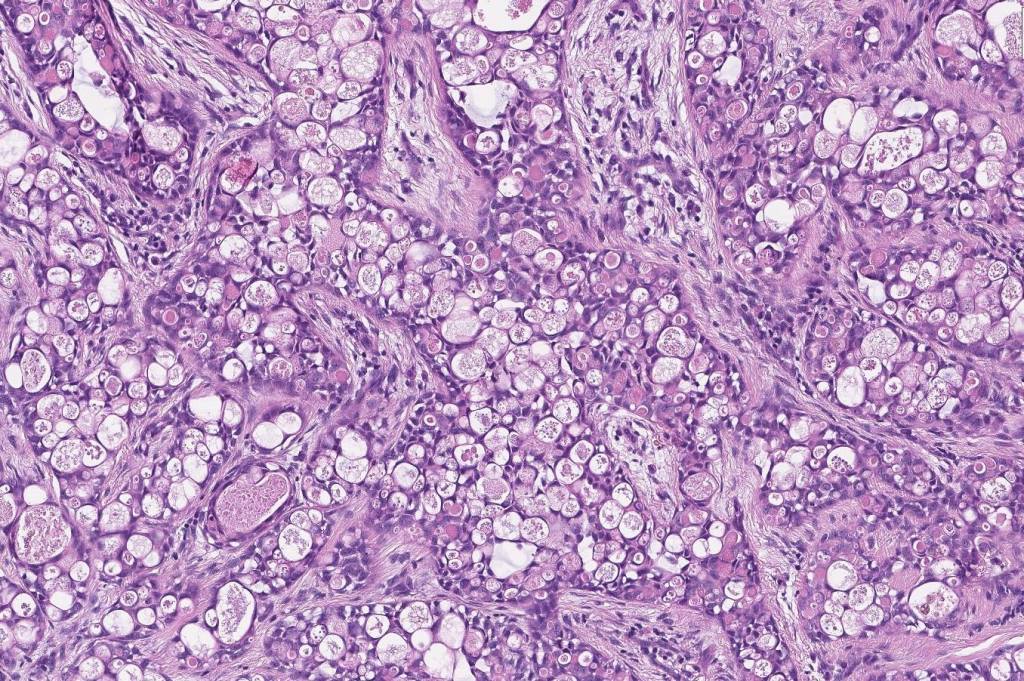

•Solid or cystic circumscribed or infiltrative dermal nodule

•Microcystic, tubular & solid patterns

•Vacuolated/granular/bubbly eosinophilic cytoplasm

•DPAS +ve luminal content

•Low grade atypia, mitoses very sparse, absence of perineural infiltration, lymphovascular invasion or necrosis